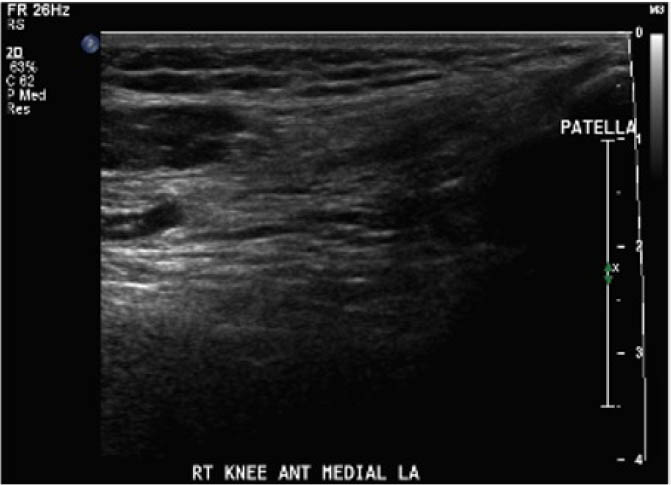

The study procedure consisted of a POCUS performed by a physiotherapist and a sonographer. The POCUS scanning procedure is presented in Appendix 1. The POCUS scans were performed in the haemophilia ambulatory clinic at patient presentation, one-week follow up, and two-week follow-up. The order of assessment was based on clinician availability. The sonographer was allowed to add additional images to the imaging protocol given their area of expertise, but the physiotherapist was instructed to acquire the images according to the scanning procedure. Ambiguous results were referred to the diagnostic imaging department for further formal investigation. Both the physiotherapist and the sonographer were blinded to each other's findings and to the results of previous scans. Methods of blinding included the use of a private clinic room and each clinician performing their assessment and documentation independently. Case report forms were placed in a sealed envelope. POCUS images were saved on the hard drive of the POCUS machine (GE Logiq) using an anonymous participant identification number.

Outcomes were assessed at presentation, one-week follow-up, and two-week follow up, resulting in a three-week study period. For the primary objective, the outcome of interest was the binary decision on the presence or absence of blood within the joint. As the technique and protocol in this study was specific to haemophilia, the criteria used to distinguish blood from effusion on ultrasound was blood presents as a complex fluid collection with mixed echogenicity and displaceable speckles on real time compression and effusion presents as simple anechoic fluid with the absence of echoes [35]. In the context of haemophilia with no symptoms suggestive of infection, complex effusions with mixed echogenicity can be assumed to represent haemarthrosis based on previous studies that have documented the accuracy of this approach using joint aspiration [35]. The physiotherapist completed the scanning protocol and interpreted the findings to make the binary assessment. Since interpreting ultrasound falls outside the scope of the sonographer, the sonographer provided an impression on the presence or absence of blood on the case report form. The radiologist read the sonographer images and provided a final diagnosis. The radiologist also reviewed the images of the physiotherapist performed ultrasound. To compare the level of agreement, the radiologist's final diagnosis was compared to the physiotherapist's interpretation. Both the physiotherapist and the sonographer recorded inconclusive ultrasound findings as absence of blood within the joint.

For the secondary objective, criteria used to evaluate image quality were appropriate pre-sets, depth, field of view, focus, gains/time gain compensation, colour and/or power Doppler, with suitable landmarks and annotation. Image quality was evaluated by the radiologist post hoc and rated as optimal, acceptable, or sub-optimal. Optimal was defined as good image quality with optimal ultrasound settings and correct annotation/documentation. Acceptable was defined as good image quality, with one image setting that should have been better optimized or a minor error in annotation/documentation that did not impact the interpretation of the POCUS scan. Sub-optimal was defined as poor image quality with more than one image setting not sufficiently optimised or an error in annotation/documentation that impacted the radiologists’ interpretation of the POCUS scan.

Post hoc analysis of the quality of the ultrasound images is shown in Table 2. The physiotherapist-performed POCUS scans demonstrated that 84.6% of the images were rated by the radiologist as optimal, 15.4% were rated as acceptable, and none were rated as sub-optimal. For the sonographer-performed POCUS scans, 88.9% of the images were rated as optimal, 11.1% were rated as acceptable, and none of the scans were rated as sub-optimal.